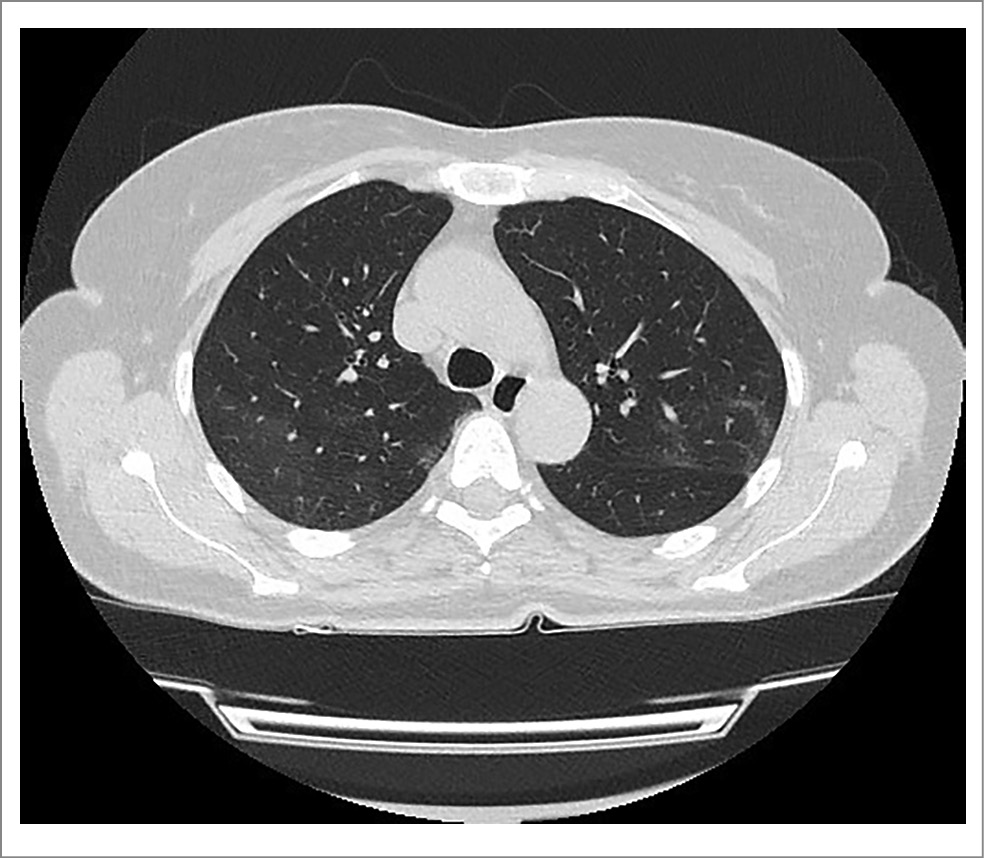

По данным КТ подтверждена картина вирусной пневмонии COVID-19, КТ-2 (рис. 6).

Рис. 6. МСКТ органов грудной клетки пациентки М. при поступлении в стационар.